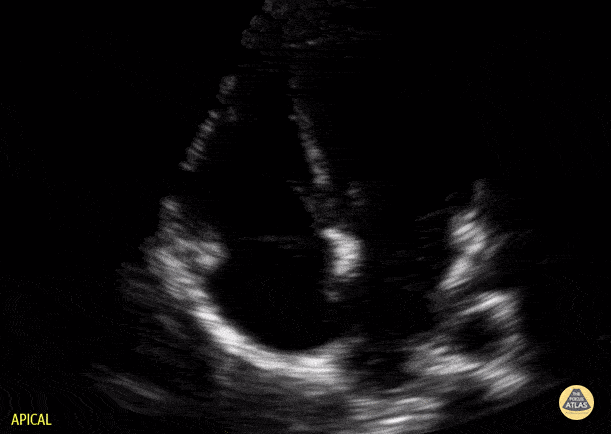

Peds-Cardiac - Older Kid Apical 4 Chamber

Normal apical 4 chamber view in a 9-year-old. Contributor: Jaron Smith, MD, Phoenix Children's Hospital